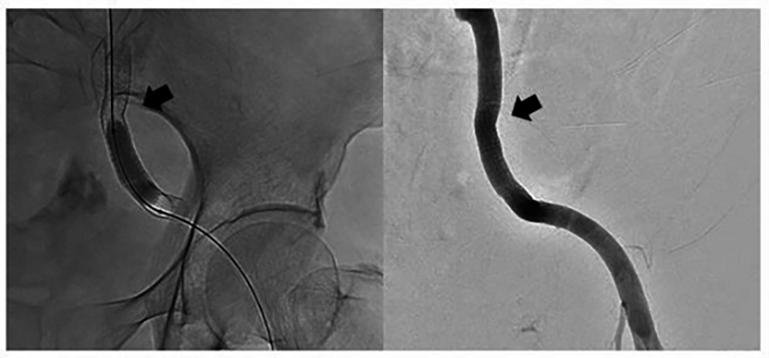

Internal jugular central venous catheterization, massive blood transfusion and

drugs administration were done as an emergency exploratory interventional

surgical was performed simultaneously. Bilateral renal artery angiography showed

no vascular anomalies and contrast spillover. However, there was obvious contrast

agent spillover on the left external iliac artery (Fig. 2). The patient was

diagnosed with a ruptured left external iliac artery pseudoaneurysm. A covered

stent, measuring 8 mm

Fig. 2.Angiography showed obvious contrast agent overflow from ruptured pseudoaneurysm on the left external iliac artery (arrow).